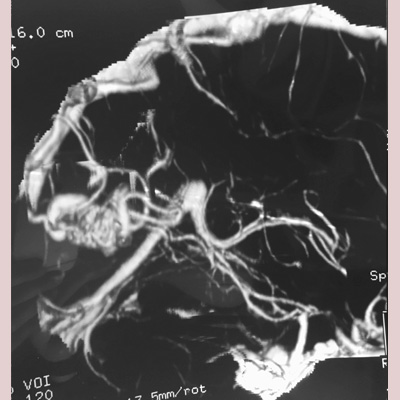

Brain Arteriovenous Malformations (AVM), as well as other Vascular Malformations are resected with sophisticated Microsurgical techniques in appropriately selected cases, or referred for Endovascular Embolization, Stereotactic Radiosurgery (SRS), or a combination of these treatment modalities with high success rates and safety and efficacy.